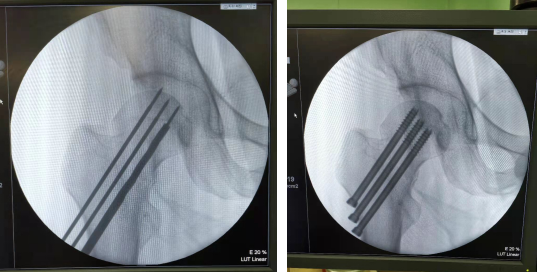

2月2日,张传开主任郝亮闫成尚医生团队为患者进行骨科机器人导航下复位股骨颈骨折手术。患者被推进手术室,麻醉、连接机器人导航装置、术中C型臂透视、手法复位后,在骨科机器人导航下精准置入三枚空心螺钉进行骨折内固定,C型臂透视显示:螺钉位置与术前规划一致,固定效果可靠。手术仅花了50分钟,一气呵成,非常成功。术中出血量仅10ml,手术创口仅1厘米,术后几乎感觉不到疼痛,患者和家属都挺满意。

机器人“C臂”术中透视及钉道规划

精确置钉